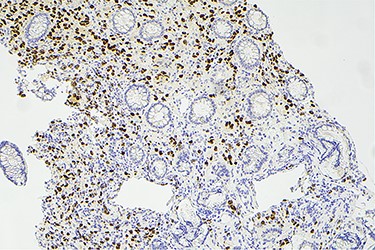

Surveillance colonoscopy in 2018 identified a fungating nonobstructing mass in the sigmoid colon (Fig. 1). Histology from a biopsy showed poorly differentiated carcinoma (Fig. 2). Given the history of breast cancer, further immunohistochemical staining was performed, which was positive for E-cadherin (Fig. 3), ER (Fig. 4), PR, GATA3 binding protein (GATA 3) (Fig. 5) and negative for Cytokeratin 20 (CK20) (Fig. 6). This confirmed metastatic invasive ductal carcinoma of breast. A positron emission tomography (PET) scan showed only the retroperitoneal mass involving the proximal sigmoid colon with no other evidence of metastatic disease (Fig. 7).

Histology slide showing positive immunohistochemical staining for E-cadherin.

Histological examination often involves multiple markers to further assist in the diagnosis. According to the literature, helpful markers include GCDFP-15, ER, PR and GATA-3 [5, 9]. Expression of CK-7 and absence of CK-20 is also commonly seen in ductal carcinoma [10]. The immunohistochemical profile for our case was positive for E-cadherin, CK-7, ER, GATA-3 and negative for CK-20 and CDX2.